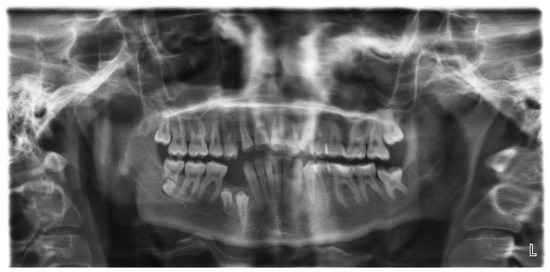

Tooth Migration in a Female Patient with Hyperdontia: 11-Year Follow-Up Case Report

2. Case Report